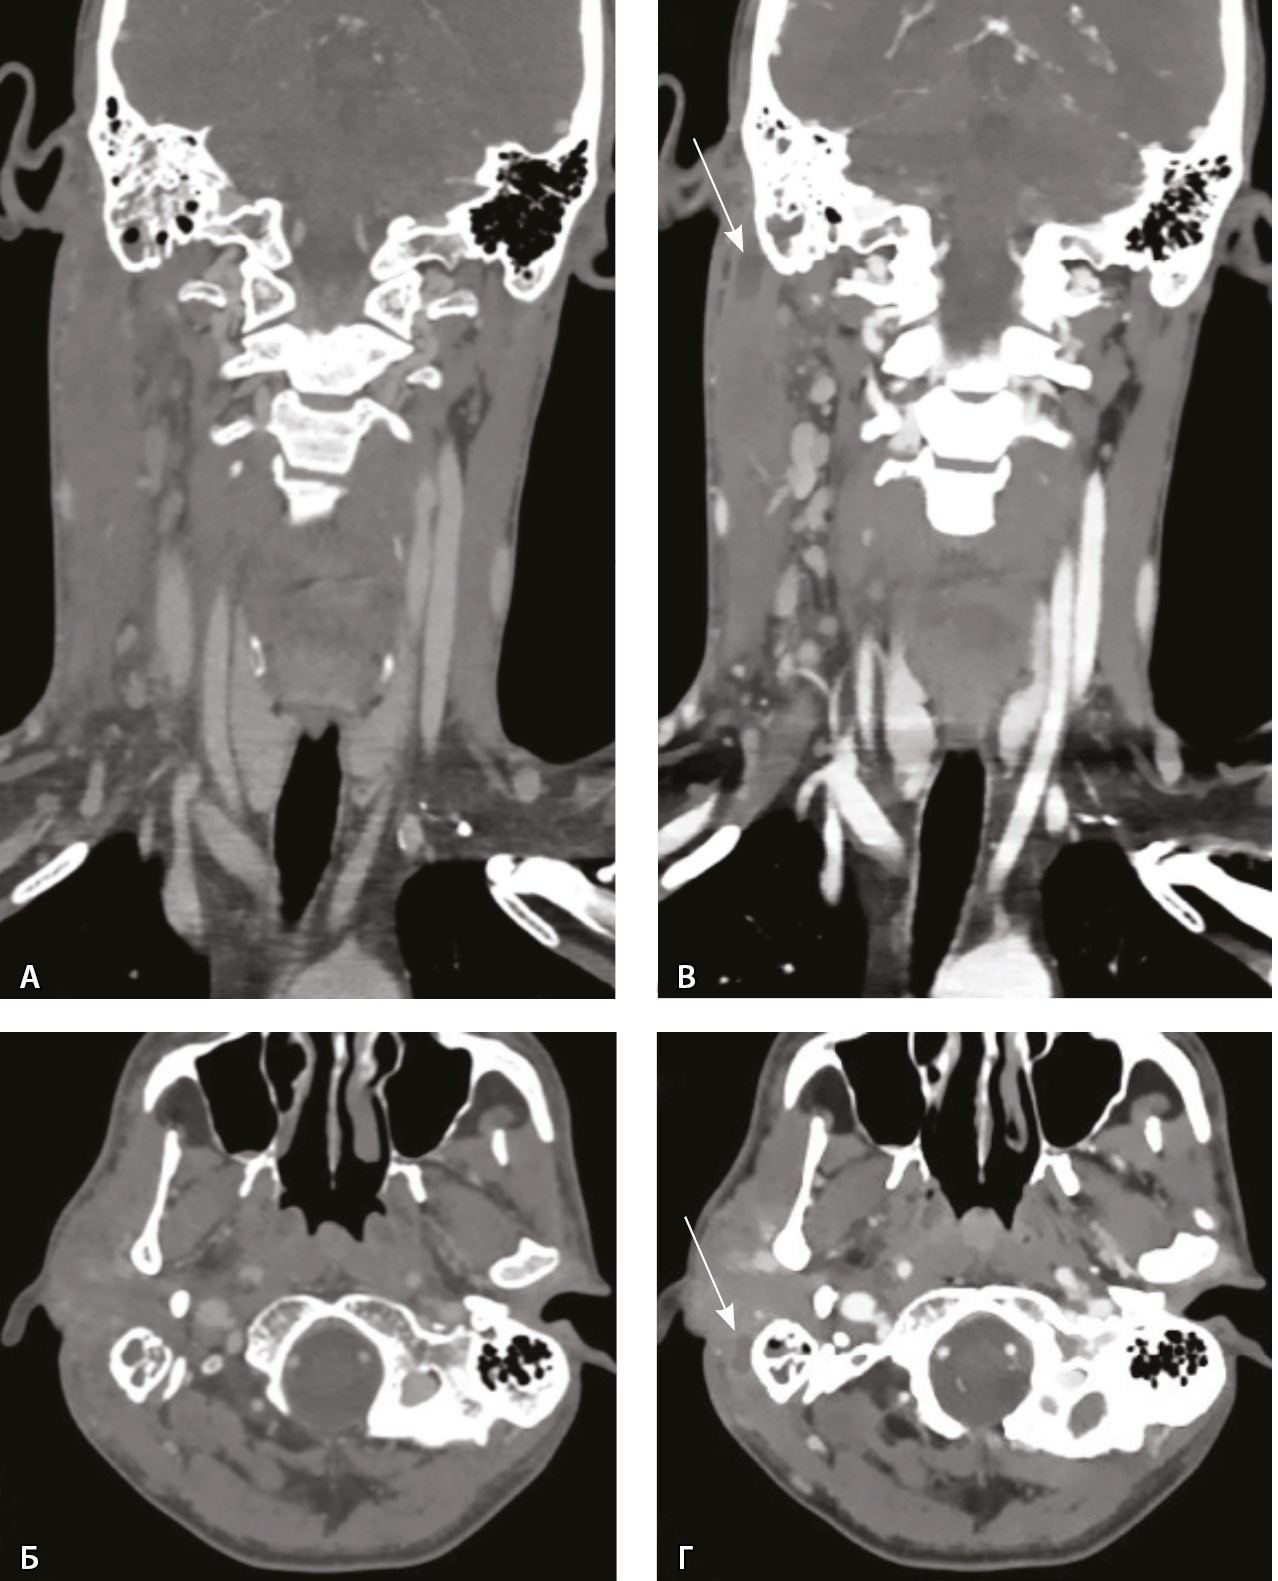

Выполнена КТ височных костей, а затем КТ шеи с контрастом. При КТ височной кости справа определялся пневматического типа строения сосцевидный отросток, практически все ячейки которого были выполнены субстратом. При этом деструктивных изменений как костных стенок ячеек, так и кортикального слоя достоверно не определено (рис. 2).

Рис. 2. Компьютерная томография височной кости, аксиальный скан, костное окно. А – в клетках сосцевидного отростка, антруме и барабанной полости справа определяется содержимое (стрелка); Б – асимметричное утолщение парааурикулярных мягких тканей справа (стрелка)

При КТ основания черепа и шеи до и после внутривенного болюсного введения йодсодержащего контрастного препарата (в рекомендуемом согласно инструкции по применению препарата объеме и с рекомендованной скоростью введения) и дальнейшем анализе сканов в абдоминальном окне начиная с уровня наружного основания черепа справа имелось явно определяемое асимметричное утолщение мягких тканей и уплотнение клетчаточных пространств. Однако на фоне утолщенных мягких тканей в режиме обычной визуализации дополнительных жидкостных образований, требующих хирургического вмешательства, не обнаружено. Так как исследование выполняли на компьютерном томографе Philips iQon Spectral CT (Philips, Нидерланды), был проведен анализ моноэнергетических изображений с низкими энергиями. Это позволило выявить в толще измененных мягких тканей на уровне сосцевидного отростка, в парафарингеальном пространстве низкоконтрастные сообщающиеся жидкостные образования – скопления гноя, которые на обычных изображениях не определялись и могли быть пропущены врачом-рентгенологом (рис. 3).

Рис. 3. Компьютерная томография шеи, венозная фаза. Фронтальная реконструкция и аксиальный скан. А, Б – обычный режим, мягкотканное окно; В, Г – моноэнергетическое изображение 40 кеВ на том же уровне: виден субпериостальный абсцесс вдоль латеральной поверхности верхушки сосцевидного отростка (стрелки), не определяемый в обычном режиме